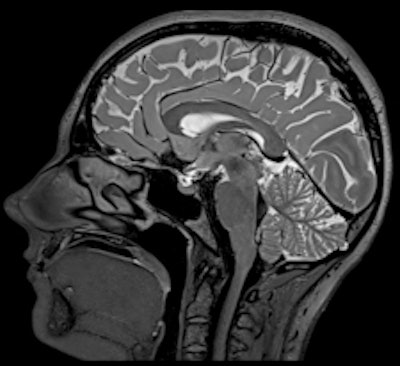

Siemens Healthcare is introducing a 3-tesla machine and is emphasizing its value as a research tool in neurology, physiology, and tissue metabolism studies. The company believes that the Magnetom Prisma sets new standards, having a gradient strength of 80 mtesla/m combined with a slew rate of 200 tesla/m/sec.

The system also offers a tandem configuration unavailable in any other commercial whole-body system, according to the vendor. The device's combination of high gradient strength and fast gradient switching speed allows for increased image quality compared with conventional devices. Due to this combination of high spatial and temporal resolution, the new machine can reportedly achieve good image quality, especially in very demanding applications. Furthermore, by combining high gradient strength with fast gradient switching speed, the Magnetom Prisma offers new possibilities in areas such as diffusion imaging, because even minor diffusion effects can be captured. Moreover, the diffusion spectrum imaging (DSI) application makes it possible to resolve fine anatomical details of the brain, such as crossing white-matter fibers by using up to 514 diffusion encoding directions, Siemens stated.